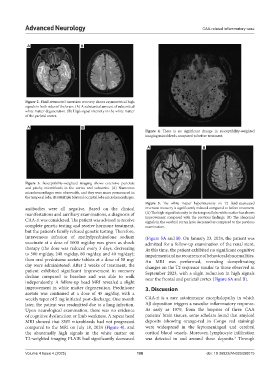

A B

Figure 4. There is no significant change in susceptibility-weighted

imaging microbleeds compared to before treatment.

Figure 5. The white matter hyperintensity on T2 fluid-attenuated

antibodies were all negative. Based on the clinical inversion recovery is significantly reduced compared to before treatment.

manifestations and auxiliary examinations, a diagnosis of (A) The high-signal intensity in the temporal lobe white matter has shown

improvement compared with the previous findings. (B) The abnormal

CAA-ri was considered. The patient was advised to receive signals in the cerebral cortex have decreased as compared to the previous

complete genetic testing and receive hormone treatment, examination.

intravenous infusion of methylprednisolone sodium (Figure 5A and B). On January 23, 2024, the patient was

succinate at a dose of 1000 mg/day was given as shock admitted for a follow-up examination of the renal stent.

therapy (the dose was reduced every 3 days, decreasing At this time, the patient exhibited no significant cognitive

to 500 mg/day, 240 mg/day, 80 mg/day, and 40 mg/day); impairment and no recurrence of behavioral abnormalities.

then oral prednisone acetate tablets at a dose of 50 mg/ An MRI was performed, revealing demyelinating

day were administered. After 2 weeks of treatment, the changes on the T2 sequence similar to those observed in

patient exhibited significant improvement in memory September 2023, with a slight reduction in high signals

decline compared to baseline and was able to walk near the frontal and parietal cortex (Figure 6A and B).